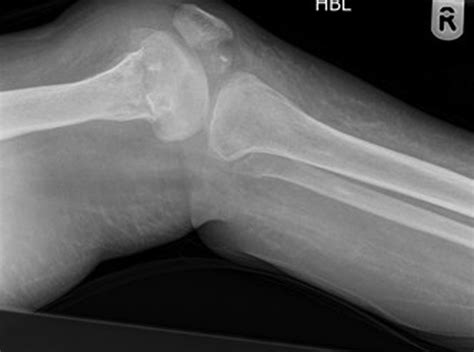

• Musculoskeletal Abnormalities: Limb hypoplasia (underdevelopment of limbs) and muscle weakness are common.